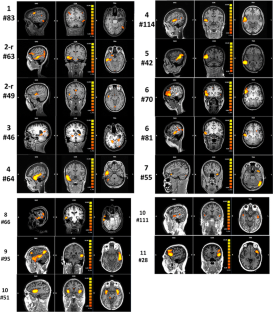

Fig. 1